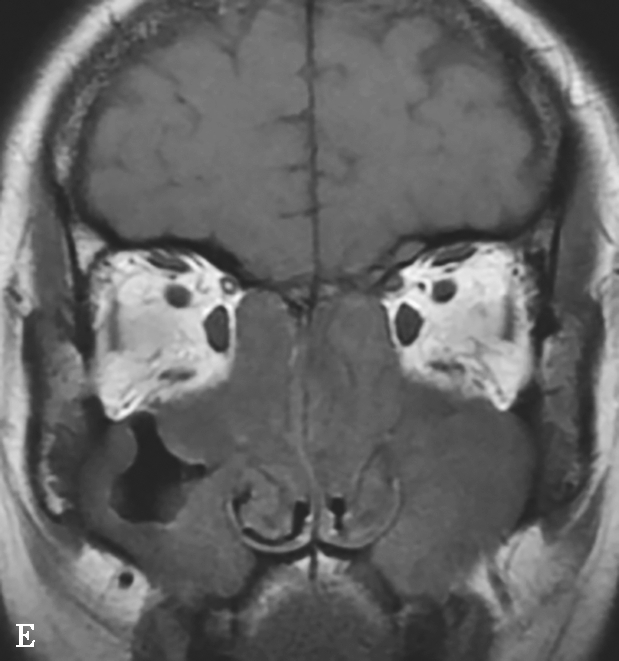

图1-3-24 嗜酸细胞增多黏液性鼻窦炎

A、B.横断面及冠状面CT骨窗,示双侧额窦、筛窦、上颌窦及蝶窦腔充填软组织影,密度不均匀,见多发斑片状磨玻璃样密度影“双重密度影”;双侧中、总鼻道见软组织影充填;C~E.横断面T 1 WI、T 2 WI及冠状面T 1 WI,示全组鼻窦窦腔充填长T 1 、混杂短到长T 2 信号影,双侧中鼻道、总鼻道及上颌窦窦口区可见小斑片状略短T 1 混杂等到短T 2 信号影